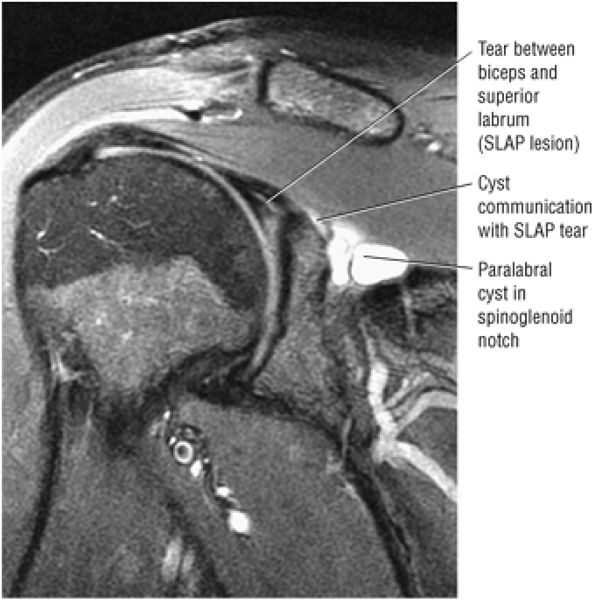

-

Interstitial tear extending from the posterior supraspinatus tendon to the anterior infraspinatus tendon. The anterior margin of the tear extends to the articular surface.

Type 2 SLAP tear extending primarily into the posterior superior labrum

Anterior inferior acromial spurring, os acromiale, and mild subacromial/subdeltoid bursitis